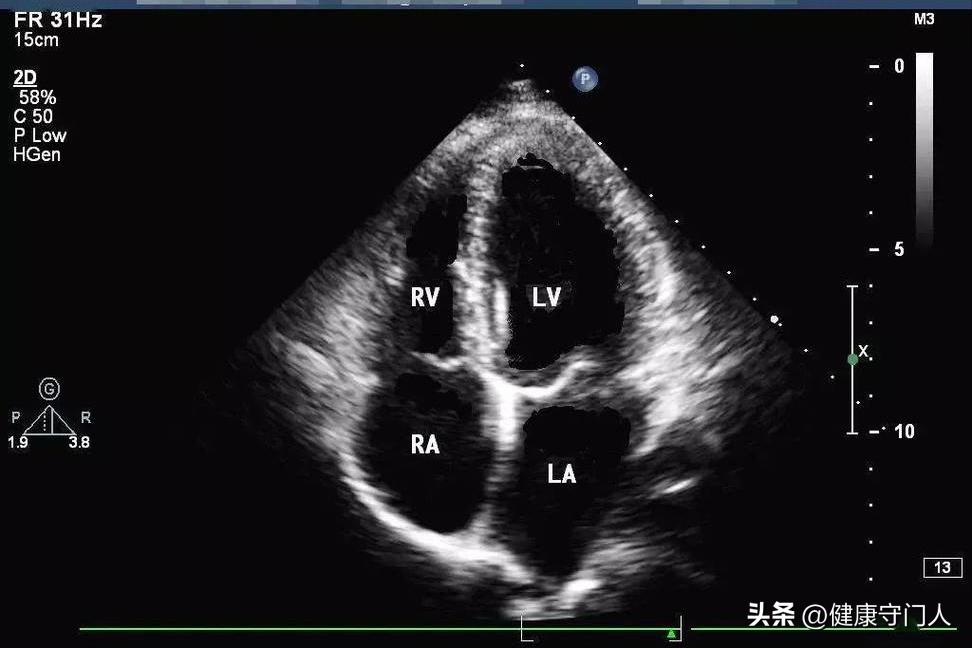

四、心脏彩超:看清结构才能下结论

心脏彩色超声检查可以理解为对心脏进行的B型超声波探查,能够清晰地观察到心房、心室以及瓣膜的具体构造和运作状态。

如果你的报告上写着:

· 左室射血分数(LVEF)在55%~70%之间;

· 心腔大小正常;

· 无瓣膜反流或只有轻度反流;

基本可以断定你的心脏结构和功能是正常的。

老年群体而言,心脏彩色超声的检测价值要高于心电图诊断结果,如果接受了一次全面的彩色超声检测pg赏金大对决试玩版,报告显示没有发现显著问题,那么确实可以安心不少。